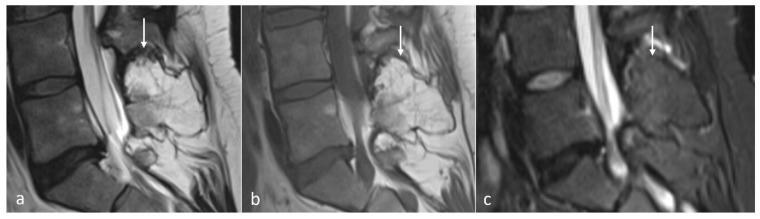

棘突的解剖结构与病理情况

Anatomy and Pathologies of the Spinous Process.

棘突起到肌肉和韧带附着点的杠杆作用。脊柱成像通常作为疼痛和神经根病的诊断检查。在解读这些通常包括X线片、计算机断层扫描(CT)和磁共振成像(MRI)的图像时,可能会遇到无数偶然或意外的发现,既有潜在无症状的,也有有症状的。孤立的棘突病变虽然不太常见,但也是可能遇到的病变类型,可能会带来诊断难题。这些病变范围包括先天性异常、创伤性病变、肿瘤以及炎症性、感染性和代谢性病因引起的病变。专门综述这些病变的文献较为稀少。本文基于作者在一家三级骨科中心10年间通过成像识别出的孤立性棘突病变,综述了一系列影响棘突的病理情况及其相关的影像学特征。为进行本叙述性综述,利用关键词“棘突”在医院图像存档与通信系统(PACS)和放射信息系统(RIS)中进行了检索,并根据影像学报告编制了一份棘突孤立性病变列表。放射科医生在脊柱常规成像中识别出这些病变时,考虑这些病变非常重要。